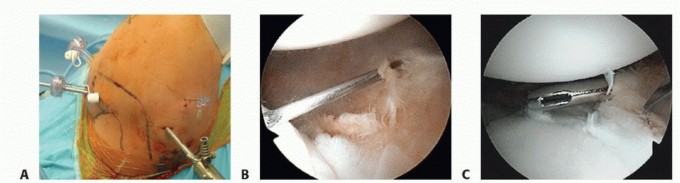

Anchor Placement and Suture Passing

Anchor placement begins at the most inferior aspect of the tear, typically at the 5:30 position for a right shoulder. This foundational anchor is the most critical; it dictates the tension of the inferior glenohumeral ligament and the success of the entire shift. The drill guide is introduced through the anteroinferior portal, ensuring a trajectory that bisects the glenoid face to avoid joint penetration (the "deadman's angle"). We utilize modern biocomposite or all-suture anchors, typically 2.4mm to 3.0mm in diameter, to minimize bone removal while maximizing pull-out strength.

Image

Once the anchor is deployed, suture passing is executed to achieve a distinct inferior-to-superior and medial-to-lateral shift of the capsulolabral tissue. Various passing devices can be utilized, including curved suture lassos or direct penetrating devices. The device is passed through the capsule first, inferior and medial to the anchor, and then through the labrum.

This "pinch" of tissue ensures that when the knot is tied (or the knotless mechanism is tensioned), the capsule is plicated and drawn up onto the articular margin, recreating the essential bumper effect. Subsequent anchors are placed sequentially moving superiorly along the anterior rim, typically at the 4 o'clock and 3 o'clock positions, depending on the extent of the lesion.